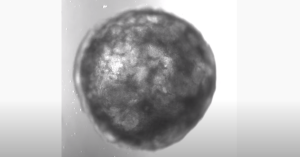

Австрійські вчені успішно виростили маленьке штучне серце. Це перший подібний мініатюрний орган з однією камерою, що самоорганізується.

Як повідомляє ТСН, фахівці впливали на людські стовбурові клітини, використовуючи шість сигнальних шляхів, які відповідають за розвиток серця у людського ембріона, внаслідок чого модель сформувалася самостійно.

Такий зовнішній вплив призводить до поділу стовбурових клітин, дозволяючи штучному органу рости і формувати нові шари під контролем учених.